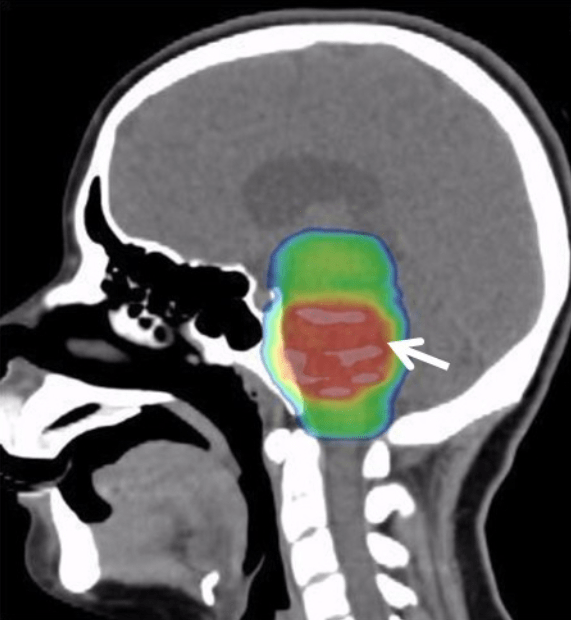

Diffuse midline glioma (DMG) is a rare but extremely aggressive brain tumor that mainly affects children and young adults. These tumors arise from glial cells—the “support cells” of the brain—and grow along midline structures like the thalamus, brainstem, or even the spinal cord. Because these areas control vital functions such as movement, breathing, and heart rate, surgery is impossible.

Header Image Source: File:Palliative Care Options for a Young Adult Patient with a Diffuse Intrinsic Pontine Glioma – Fig. 3 (cropped).png – Wikimedia Commons